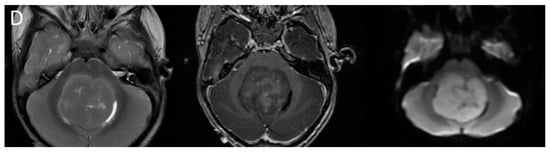

| Posterior fossa ependymoma | Fourth ventricle (PFB) or cerebellopontine angle (PFA) | Heterogeneous mass Calcifications common Intermediate diffusion (between medulloblastoma and pilocytic astrocytoma) Usually enhancing High myo-inositol on MRS |

| Supratentorial ependymoma | Frontal or parietal parenchyma | Large mass with necrosis Central chunky calcifications Diffusion restriction in two-thirds |